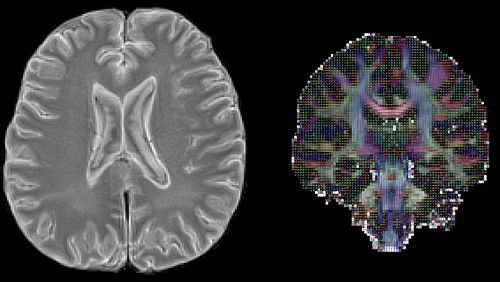

Images are among the most important media in medicine. They allow for the most precise diagnosis of injuries and diseases, progonsis, planning, monitoring, patient consenting, teaching and education, simulation, development of biomaterials etc. Under the influence of artifical intelligence, this field is currently evolving rapidly, opening up large numbers of known and unknown new opportunities. Therefore, this comptence cluster is the largest at the DBE. The research groups within this field are: Acoustic and Vestibular Research Group, Basel Muscle MRI, the Bilateral Neurocircuitry Lab, Digital Dermatology, the Center for medical Image Analysis and Navigation, Computational & Translational Pathology Lab, Magnetic Resonance Physics and Methodology, the Medical Imaging Research Group, and Translational Imaging in Neurology ThINk.